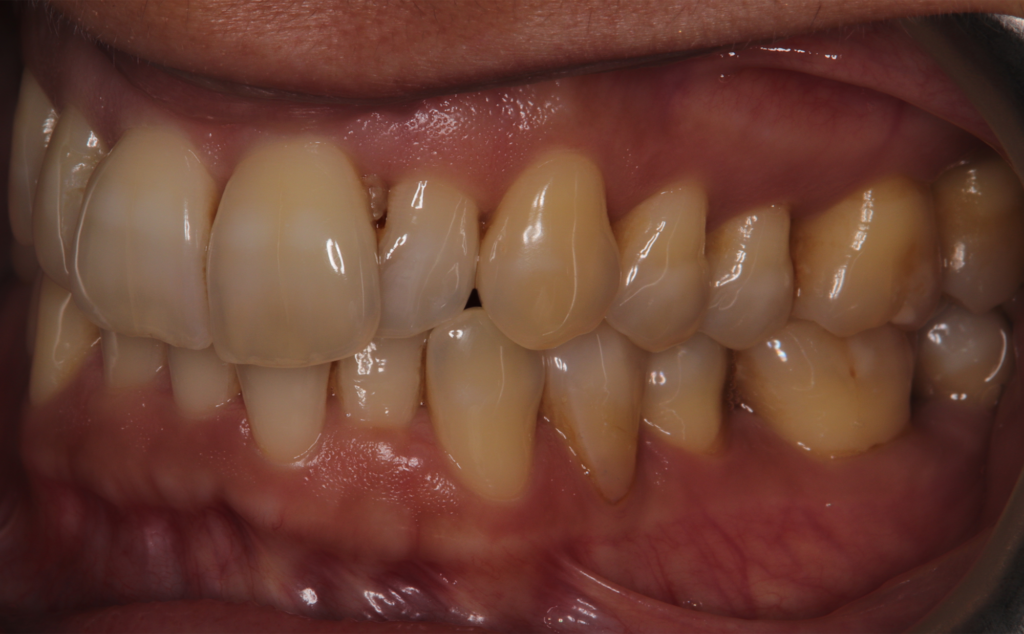

The patient, having completed a periodontal treatment phase, presented with significant aesthetic and functional concerns due to moderate crowding in both arches and a pronounced anterior crossbite. Clinical examination confirmed the need for comprehensive realignment, particularly in the anterior region. Although the patient had a history of periodontal issues, radiographic evaluation showed no signs of active disease. Based on these findings, the treatment plan was designed to carefully modulate orthodontic forces to protect the occlusion and surrounding tissues while addressing the misalignment.

To correct the misalignment and anterior crossbite without compromising tissue stability, a slower orthodontic treatment plan was devised using the Spark Advanced clear aligner system. The initial phase involved 36 aligners designed to gently expand and realign the dental arches, limiting the rate of tooth movement. Strategic interproximal reduction (IPR) was performed in the anterosuperior region (between teeth #21 and #11) to create the necessary space for proper alignment while avoiding excessive loading on the tissues.

To refine the results and enhance aesthetics, a second phase incorporating an additional 17 aligners was introduced. During this refinement stage, careful IPR in the lower arch helped harmonize the midline and achieve a balanced occlusion. Once satisfactory alignment was reached, provisional composite restorations were placed on the upper lateral incisors to aesthetically close any interproximal gaps.

At the conclusion of the treatment, the patient achieved excellent dental alignment and a stable occlusal relationship, particularly in the anterior region. Radiographs and clinical assessments confirmed that there was no further bone loss and that previous improvements were maintained. The aesthetic enhancement from the composite restorations further contributed to the overall success of the treatment.